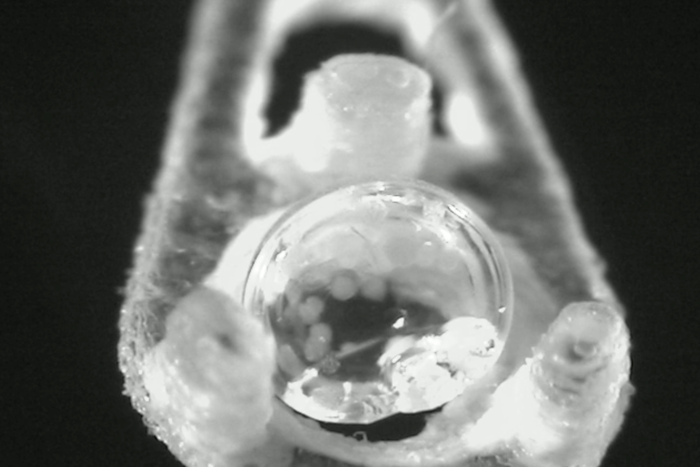

将胰岛细胞包裹的小液滴在极低温度下储存长达9个月,然后使用新的复温技术使它们恢复到移植前的原始状态。图中显示的是该团队研究的一种方法,它使用激光快速重新加热冷冻保存的胰岛液滴。

通过使用专用的cryomesh系统,多余的冷冻保护液被去除,从而可以以每秒几万度的速度快速冷却和重新加热,同时避免了成冰的问题,并将毒性降至最低。